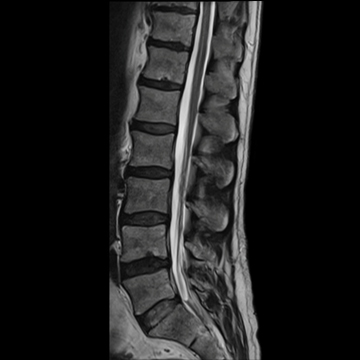

全脊椎

T1 TSE, 448 matrix

T2 STIR, 384 matrix,